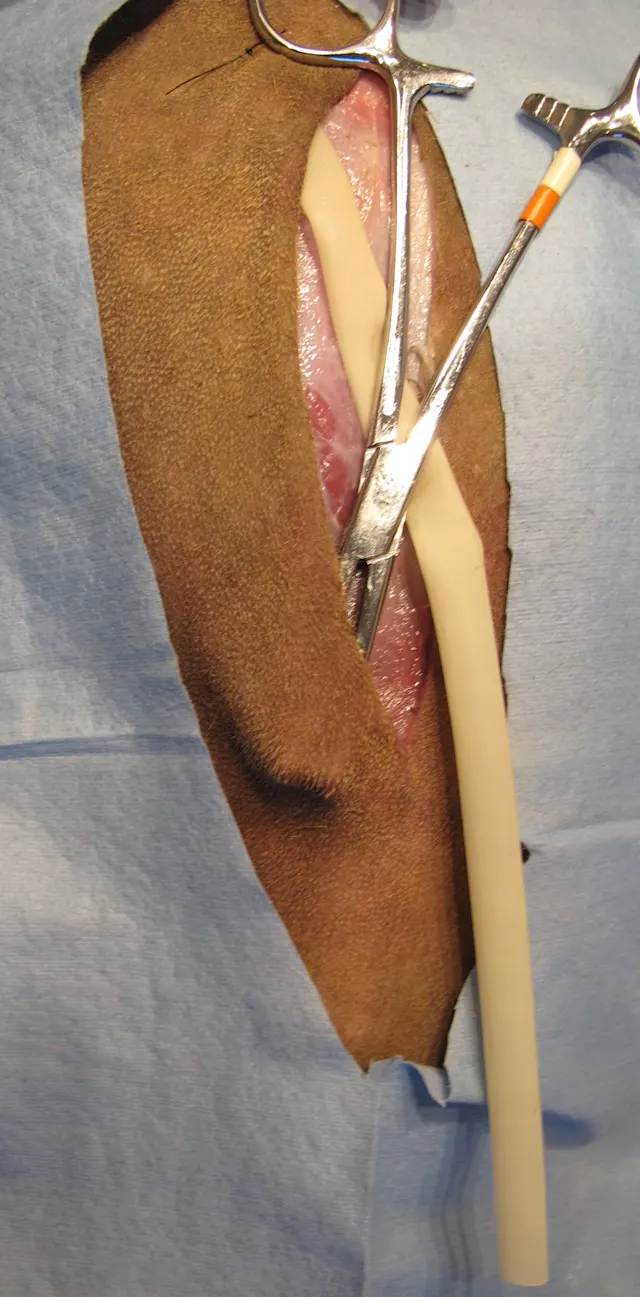

Step 4

Insert the hemostats through the incision to facilitate exteriorization of the drain.